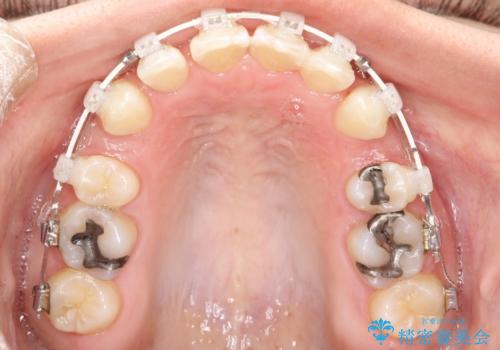

- 審美装置

- 2年2ヶ月

- 口元が出てるのが気になるとのことで来院されました。

上下左右前から4番目の歯を抜歯して前歯を後方に下げて、口元を下げる計画としました。